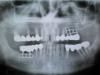

pistons777 Опубликовано 15 сентября, 2011 Поделиться Опубликовано 15 сентября, 2011 Здравствуйте! Уважаемые врачи, прошу вашего профессионального совета по комплексному лечению (удалению пластинчатых имплантов и восстановлению зубов). Интересует технология (последовательность) удаления и возможные планы восстановления всех зубов. Пластинчатые импланты были установленны около 10 лет назад моему отцу (ему 60+ лет)Нижний имплант не сильно беспокоит, а с верхним на протяжении всего времени были проблемы. На сегодняшний день верхний имплант шатается и не выполняет своих функций. Специалист который смог бы этим занятся - в поиске, и пока не найден, хотелось бы услышать советы врачей на данном форуме. Спасибо! Ссылка на комментарий

x3m Опубликовано 15 сентября, 2011 Поделиться Опубликовано 15 сентября, 2011 сложность из за большой потери кости?да.чтобы установить новые имплантаты - нужен достаточный объем кости, которого в этом случае нет.кость восстанавливается костнопластическим материалом. В любом случае оставлять эти импланты нельзя. Я правильно понимаю?даА как, в "двух словах" удаляются такие импланты (распиливаются, выдёргиваются или ...?)снимаются коронки с резца и клыка и вместе с имплантатом все "вынимается" (имплантат на верхней челюсти не фиксирован в кости, на нижней - нужно помочь ему выйти - сделать щель между имплантатом и костью и вынуть его). как вариант - отпилить подвесную коронку от коронки на своем зубе и оставить (пока что) коронки на зубах.имплантат с подвесными коронками удаляется.судьбу коронок на своих зубах решают "по ходу пьесы". с винтообразными имплантами понятнно, выкручиваютсянет, выпиливаются. если прижились.если нет - вынимаются пальцАми Ссылка на комментарий

Dr. Surkin Опубликовано 15 сентября, 2011 Поделиться Опубликовано 15 сентября, 2011 В любом случае оставлять эти импланты нельзя. Я правильно понимаю? Верхний 100% удалять, а нижний - посмотрите с доктором внимательнее - по этой рентгенограмме он еще не так плох. Возможно еще будет служить. Ссылка на комментарий